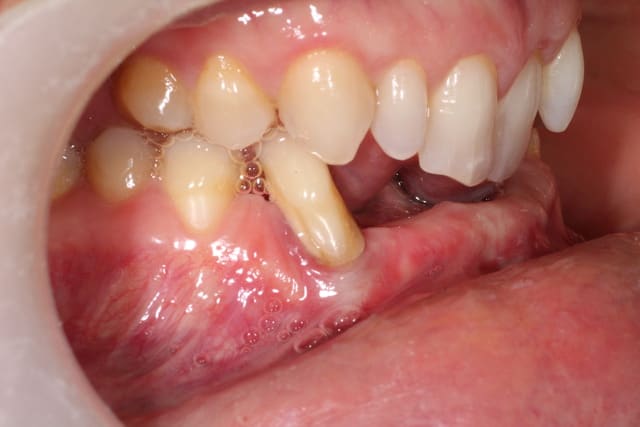

le plan de traitement consiste a poser 4 implants 43 42 33 32 et un bridge de 6 éléments.

Je viens d'extraire 42 et de débuter l'ortho.

henri, il y a 3 mm au niveau des canines, et un bridge de 6 éléments sur 2 implants, je trouve cela un peu chaud.

Voici 3 possibilités traité sur la maquette mandibulaire.

Sans hésiter j'opte pour le prélèvement symphysaire. tu n'es pas obligé de greffer au niveau des 31 et 41. Ce qui te laisse suffisamment d'os pour reconstruire les sites implantaires (4 implants, je suis de ton avis). Attention à la fermeture par contre, il y a pas mal de tension musculaire à ce niveau et la dissection du lambeau n'est pas sans risque sur le rameau labial du nerf mentonnier.

pose de 2 implants de diam 3.3 en 33 et 43

et 2 implants monoblocs en 32 et 42 pour sécuriser le traitement.

Les implants de 3.3 et les monoblocs sont parfaitement fiables aujourd'hui.

Marc pour avoir eu les fichiers dicom et le modèle "en vrai" dans les mains, c'est très très fin et très très dense

je pense sincèrement que les options d'augmentations sont plus sages...et perso, j'ai ma préférence pour un bloc usiné chez biobank...juste à ouvrir (après ostéotension, là on est tous d'accord là dessus...) et ostéosynthèser, une membrane pour protéger et zou